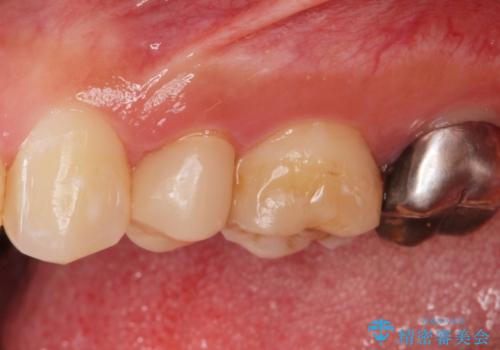

白くて適合の良い被せ物が入りました。

セラミックは劣化することがなく虫歯の再発のリスクが低くなります。

- ジルコニアクラウン・仮歯 12.1万円費用は治療当時の料金となります